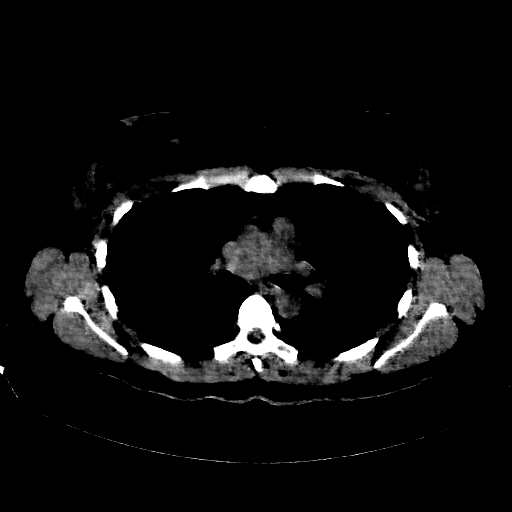

Original NATIVE CT scan (input)

Full window (WL 1023.5, WW 4095 β†’ Low βˆ’1024, High +3071)

Lung window (WL -600, WW 1500 β†’ Low βˆ’1350, High +150)

Mediastinum window (WL 40, WW 400 β†’ Low βˆ’160, High +240)